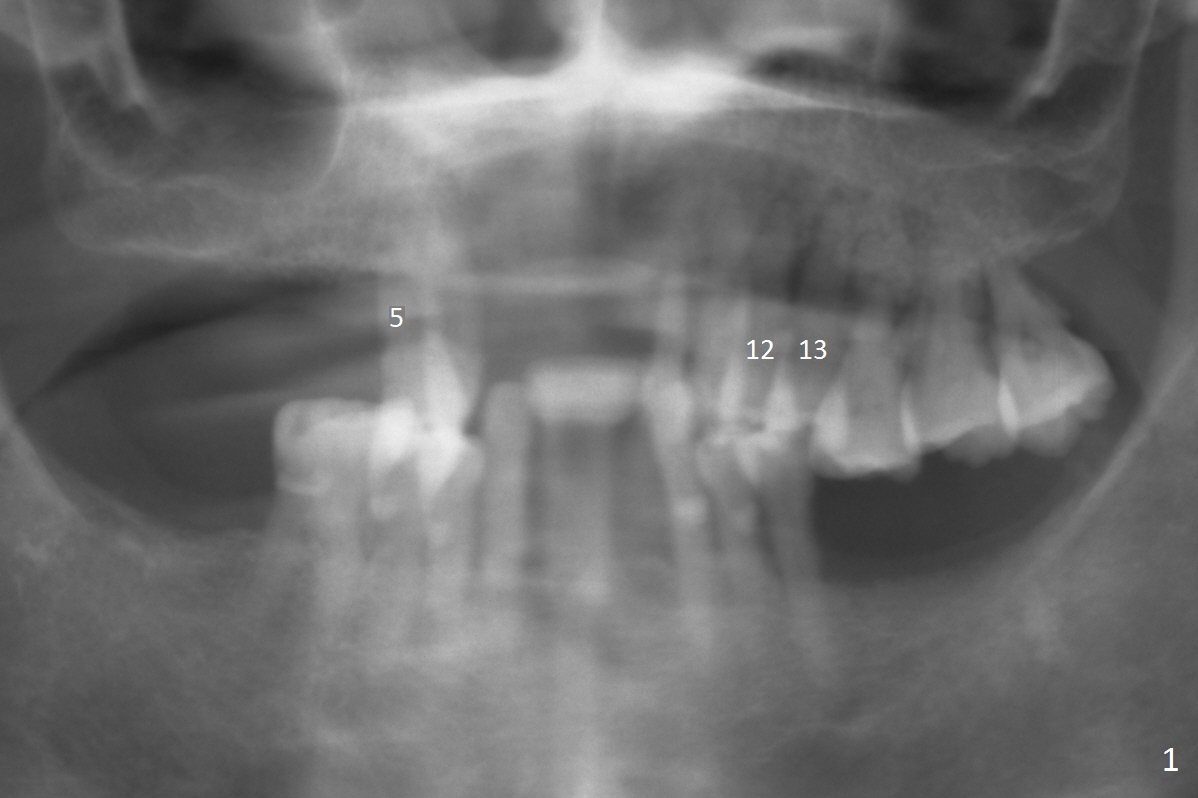

A 65-year-old woman has an upper partial denture and 3 mobile teeth (Fig.1 : #5,12,13). She wants to keep the RPD. The loose teeth are replaced by implants. There is enough bone height (Fig.2). Initial osteotomy depth will be 14 mm. Insert parallel pin(s) and take PA.